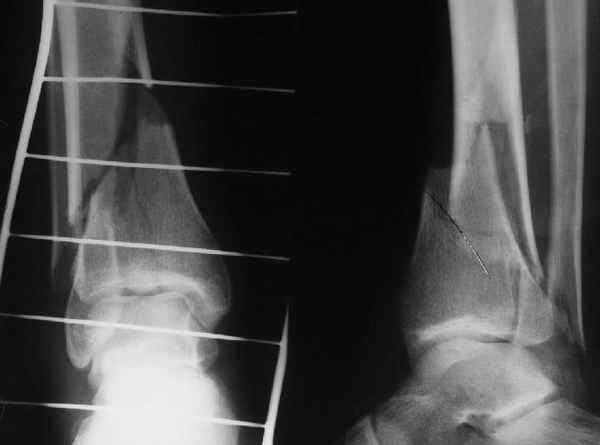

АЧ>Степень относительности этой стабильности все-таки довольно сильно может варьировать. Locked plate в сравнении с эластичным интрамедуллярным фиксатором - две большие разницы

Да и нет! Зависит от перелома и способа остеосинтеза. А результат? (01)

Мы же говорили о проксимальном плече. При переломе tibia, конечно, речи о двух Y-спицах нет. Еще раз о них - пружинящая подвижность без "срезающих" перемещений фрагментов - дополнительный стимул к образованию периостальной мозоли.

А в данном случае - у нас был бы применен locked nail с еще меньшими дырочками на коже и с возможностью полной нагрузки немедленно после операции. Какие тут аргументы в пользу выбора пластины, а не интрамедуллярного гвоздя?

Классически показанием для locked nail яв-ся зоны BC CD, до появления LCP показания к locked nail несколько расширялись в зоны AB и DE

Аргументы: перелом достаточно низкий, трудно будет ввести 3-и блок. винта, а учитывая характер перелома на 2-х дистальных винтах я бы не рекомендовал немедленную полную нагрузку.